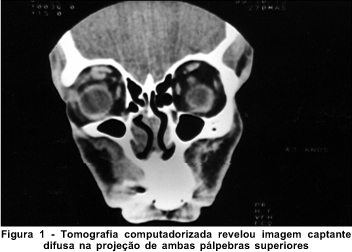

Paciente do sexo masculino, negro, 43 anos, registro de número 500453 do Hospital Universitário Professor Edgard Santos. História de tumefação palpebral bilateral iniciada há 8 meses, apresentando regressão espontânea pouco tempo após à esquerda. Em uso de medicações para hipertensão arterial sistêmica há cerca de 3 anos. Provas de função renal, ultra-sonografia orbitária, testes alérgicos e exames da função tireoidiana resultaram normais. A visão era igual a um em ambos os olhos. O exame oftalmológico revelou, de anormal, edema bipalpebral à direita, de consistência elástica. A tomografia das órbitas revelou imagem captante nas pálpebras superiores (Figura 1). Foi submetido, sob anestesia local, à orbitotomia anterior direita superiormente. O estudo histopatológico do material obtido revelou processo inflamatório crônico discreto, inespecífico, associado a edema. Diante da possibilidade diagnóstica de pseudotumor inflamatório linfocítico orbitário foi instituída corticoterapia sistêmica com prednisona na dose de 80 mg/2 dias, 60 mg/2 dias, 40 mg/2 dias e manutenção de 20 mg/dia por dez dias. Ocorreu regressão do edema bipalpebral à direita. No entanto, o paciente apresentou níveis glicêmicos em torno de 500 mg/dl, o que fez com que fosse suspensa a corticoterapia, levando ao ressurgimento do edema bipalpebral bilateralmente (Figura 2).

A tomografia computadorizada pode mostrar edema dos tecidos moles orbitários(5) ou ainda, um padrão heterogêneo destes tecidos compatível com a natureza granulomatosa do problema(2). No entanto, Cockerham, Hidayat, Cockerham, Depper et al.(2) citaram que a ressonância nuclear magnética revelou, tão somente, uma expansão pré-septal não-específica. Esse fato nos leva a reservar o diagnóstico de síndrome de Melkersson-Rosenthal apenas para os pacientes que apresentem edema facial recorrente associado a achados histopatológicos compatíveis com os anteriormente citados.

O paciente por nós estudado apresentou aspectos recentemente descritos na literatura(2), ou seja: apresentação monossintomática da síndrome, imagem à tomografia computadorizada compatível com expansão de tecidos moles e finalmente à histopatologia, linfangite granulomatosa confirmando o diagnóstico.